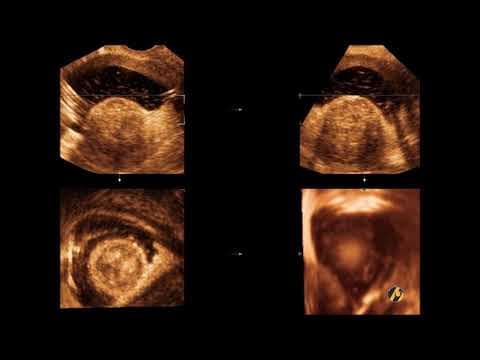

3dsis-submukozni-miomi